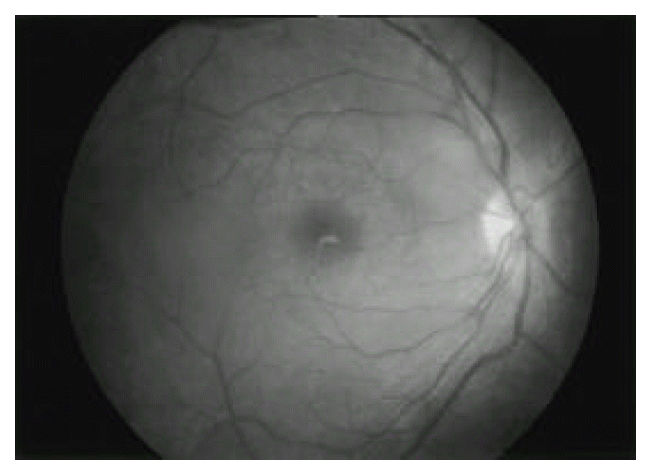

Initially he was treated with indomethacin 50 mg/day, sulfasalazine 2g/day, methotrexate 7.5 mg/week and colchicine 1.2 mg/day. Because of persisting, painful swelling of the right knee, methotrexate was increased to 15 mg/week, and intra-articular injection of triamcinolone acetonide 40 mg was done. While being treated, recurrent acute iritis with hypopyon, posterior uveitis and papillitis in both eyes (Figure 3 & 4) were developed. Prednisolone 40 mg/day and cyclosporine 5 mg/kg/day were prescribed.

Fig. 3.

Fundus photograph of the right eye shows haziness due to posterior vitritis. There are elevation and blurring of the optic disc suggesting papillitis.